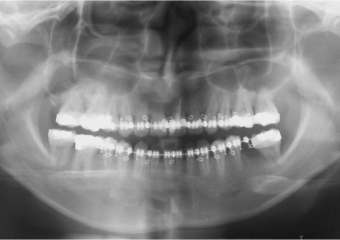

Raio x panorâmico inicial

Raio x panorâmico após a cirurgia